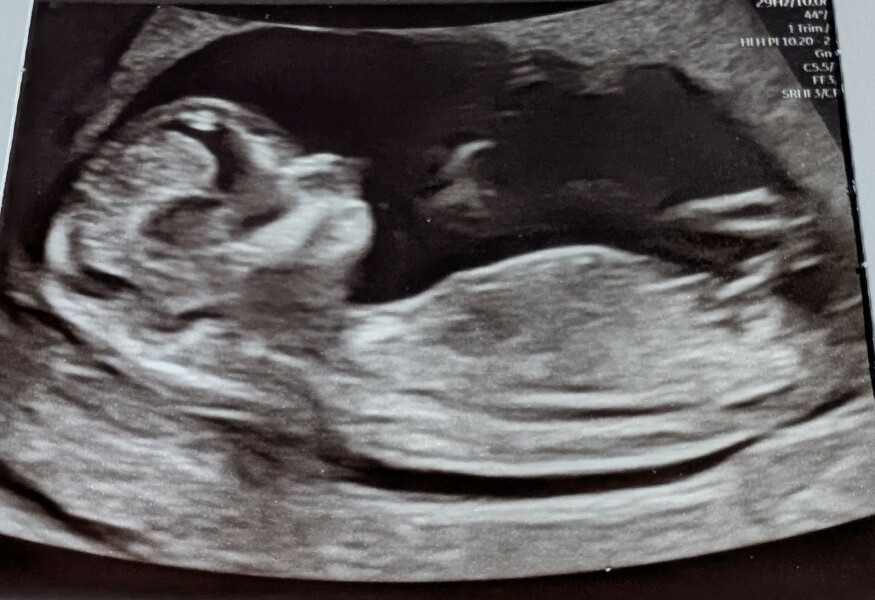

RavensMom24 · 22/04/2025 16:31

Just had my scan, I was measuring ahead at 13+5 weeks! New due date is 23/10.

I’ve always been rubbish with nub theory but I’ve attached my pics - any ideas? I have booked a private gender scan next week to find out so I will confirm then. I have absolutely no preference personally just highly impatient and want to know more about little peanut🥰

Due October 2025

@RavensMom24 Such good pictures you got!

To me it’s looking like a definite boy.